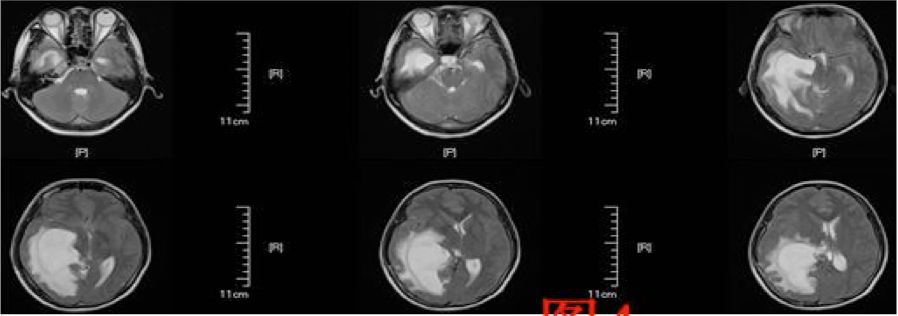

患者于术后第64天再次入院,入院后行头部MRI(图4)检查提示右侧侧脑室颞角、后角扩张并周围脑组织水肿、中线明显移位,并行腰穿测压为280cmH2O,诊断为右侧侧脑室三角区脑膜瘤切除术后孤立颞角综合征,遂于术后第68天行侧脑室颞角腹腔分流术,分流管为美敦力可调压力分流管,术中设定压力范围为105~125mmH2O,术后复查头部CT以及MRI(图5、6)。

图5. 显示V-P分流术后复查头部CT。

图6.显示V-P分流术后复查头部MRI。

术后患者头痛恶心呕吐症状消失,恢复良好出院。